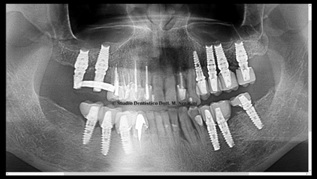

Control two months after loading on the right side and sixteen months on the left side (Figure 29).

Figure 29: Control two months after loading on the right side and sixteen months on the left side.